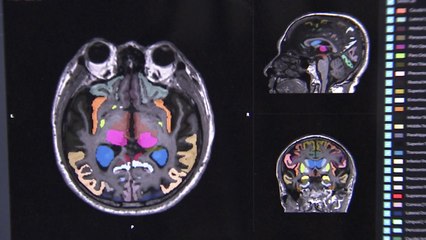

세계적으로 인구 고령화의 속도가 빨라지면서 치매 발병률도 매년 늘고 있는데요. br br 국내 연구진이 치매 유발 독성 물질의 고감도 촬영기술을 개발했습니다. br br 증상이 없는 상태에서도 혈액만으로 독성 물질 조기 발견이 가능해지면서 치매 예방에 큰 도움이 될 것으로 기대됩니다. br br 오선열 기자입니다. br br [기자] br 100세 시대에 가장 두려운 질병 '치매'. br br 치매를 유발하는 독성 단백질, '베타아밀로이드'를 측정하는 뇌 촬영 기술은 가격이 비싸고 대형 병원에서 이뤄지기 때문에 대규모 신속 검사가 어렵습니다. br br 국내 연구팀이 기존 검사법의 한계를 극복하기 위해 독성 단백질을 쉽게 발견할 수 있는 화학 합성물을 개발했습니다. br br 형광 물질로 이뤄진 합성물이 독성 단백질과 섞이면 빛을 띠기 때문에 소량의 '베타아밀로이드' 농도도 측정할 수 있게 된 겁니다. br br [김종승 고려대 화학생명공학과 교수 : 치매가 많이 발달한 상태에서 하니까 고칠 수가 없는 거예요. 그래서 조기에 발견하면 그게 가능한 거죠. 저희가 개발한 형광물질로 독성 단백질이 쌓여 있는 것이 조금 있을 때도 그것을 감지해낼 수 있고….] br br 연구팀의 목표는 전 국민을 대상으로 무증상 상태에서 치매 유발 물질을 미리 측정하는 겁니다. br br 그러기 위해선 혈액에서 독성 단백질을 측정하는 안정된 기술 확보가 필수입니다. br br [허민석 씨젠 의료재단 호남검사센터 의료부장 : 혈액 바이오 마크를 검출할 수 있는 이런 기술이 된다면 그러한 검사 자체의 장벽이 낮아지게 돼서 더 많은 사람이 저렴한 비용으로 편하게 검사를 받을 수 있어서….] br br 광주 치매 코호트 연구단은 지난 10년 동안 지역 사회를 대상으로 관리한 치매 위험군의 혈액을 활용해 측정 연구에 나섰습니다. br br 연구팀은 5년 안에 국민 건강검진을 통해 치매 유발 물질을 발견할 수 있는 초고속 검사가 가능할 것으로 예측했습니다. br br [이건호 조선대학교 교수, 한국세포생물학회장 : 지역의 60세 이상 어르신을 대상으로 정밀의료 검사를 실시한 결과와 코호트를 구축하고 있기 때문에 이른 시간 내에 이번에 새롭게 개발된 형광물질 진단 기법의 유효성을 입증해 낼 수 있다, 이렇게 말씀드릴 수 있습니다.] br br 국내 연구팀이 세계 최초로 개발해 국제 유명 학술지에도 실린 치매 조기 진단 기술. br br 100세 시대를 살아가는 국민의 삶의 질을 높이는 데 한몫할 ... (중략)br br YTN 오선열 (ohsy55@ytn.co.kr)br br ▶ 기사 원문 : ▶ 제보 안내 : , 모바일앱, social@ytn.co.